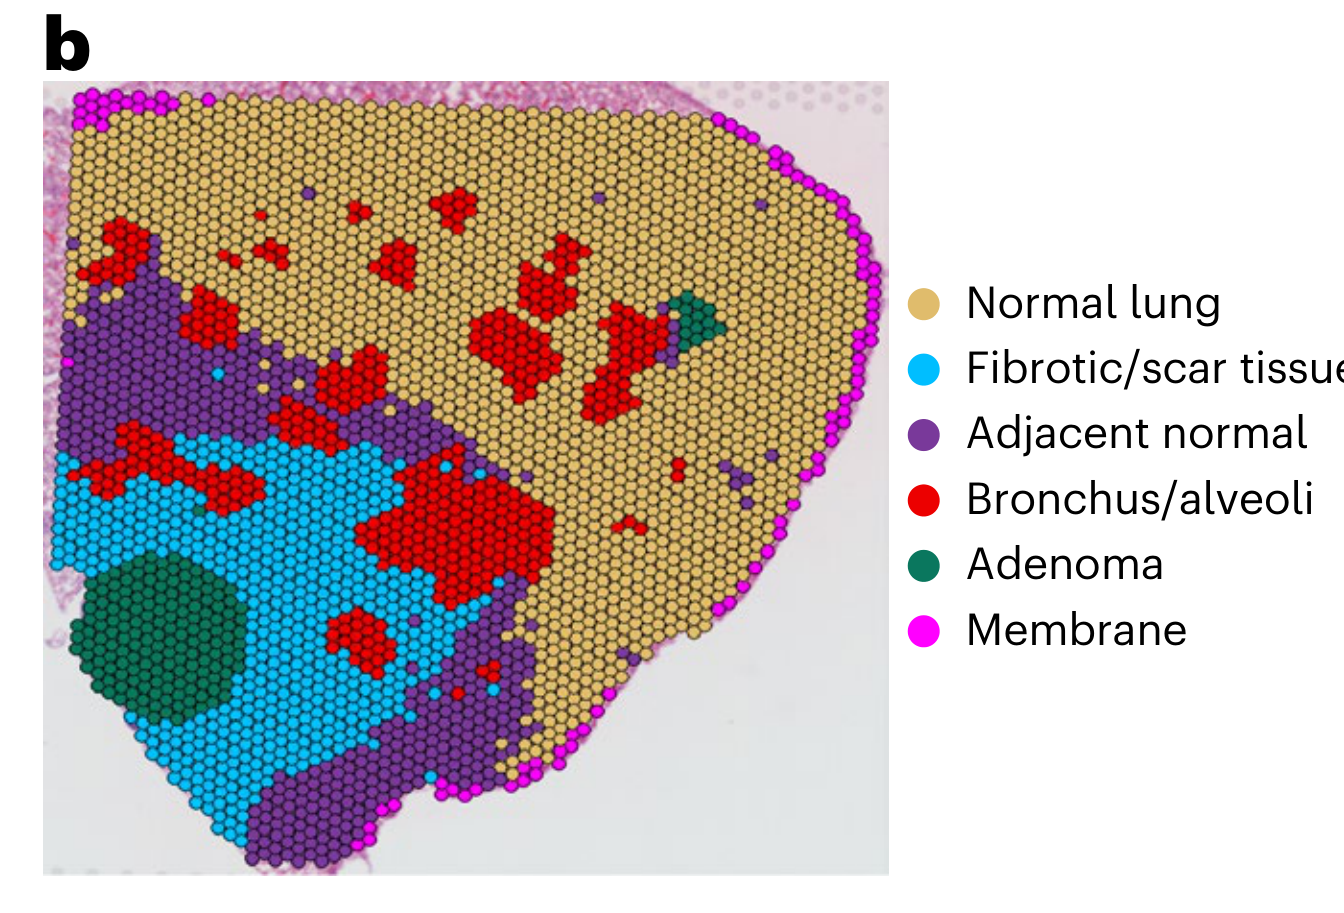

What is the spatial distribution of disease subtypes?

What is the tissue morphology and architecture?